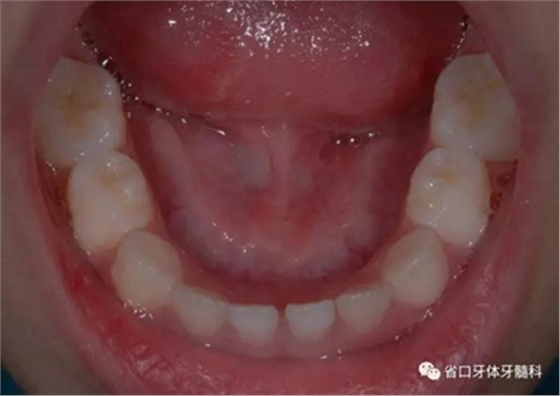

圖4 正面牙相(2015年1月)